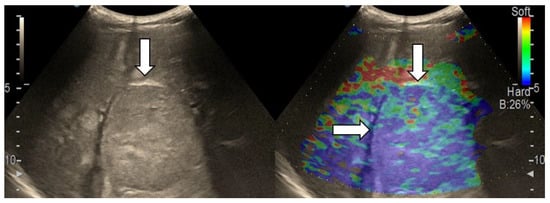

3.4. Real-Time Tissue Elastography